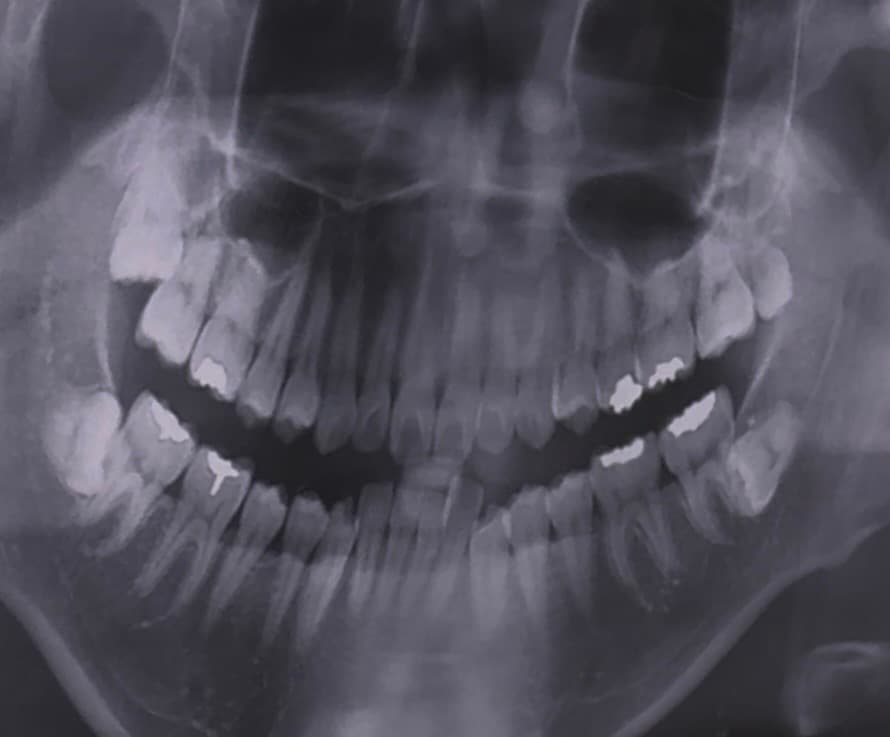

병원에서 윗쪽에 표시한 사랑니에 충치가 있다고 하는데 그냥 뽑는게 맞나요?

반듯하게 난건 나중에 스페어로 쓸수있다 그래서 고민이에요...